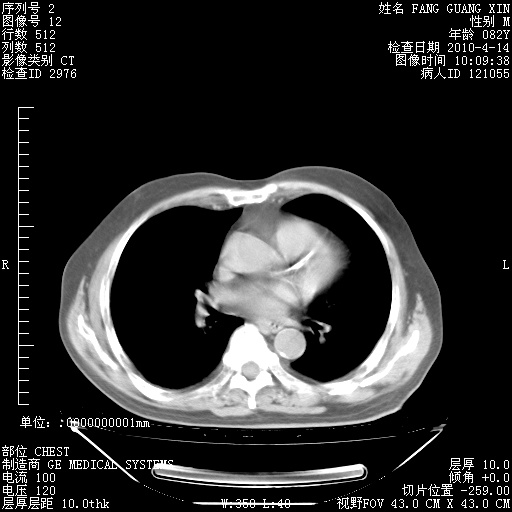

4月14日肺部CT

23.JPG

24.JPG

25.JPG

26.JPG

肺部CT平扫未见异常。